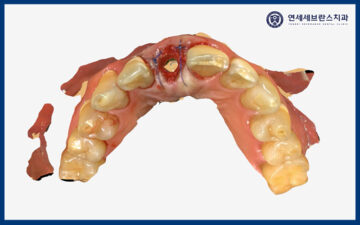

그리고 지대주와 임시치아를

구강스캐너를 통해 채득하였습니다.

구강 스캐너를 통해 제작된

지대주와 임시치아를 임플란트에

결합한 뒤 접착하였습니다.